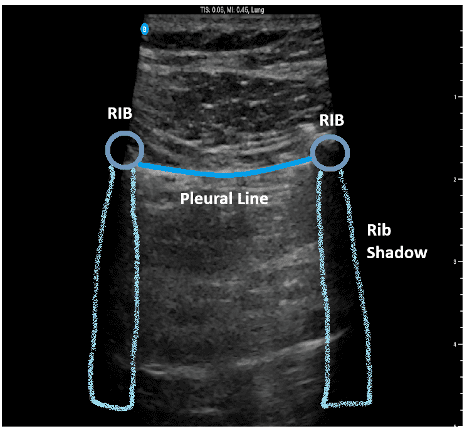

Figure 1. Normal Lung Ultrasound Anatomy

This image demonstrates normal ultrasound lung anatomy. For optimal imaging, center the pleural line on the screen and position the ribs on either side; avoid placing a rib directly in the center of the image.